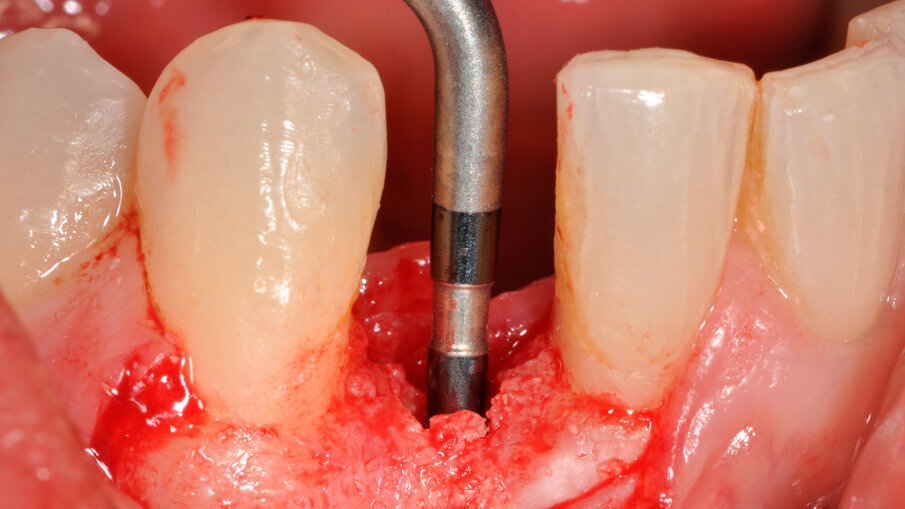

Zavedení implantátu